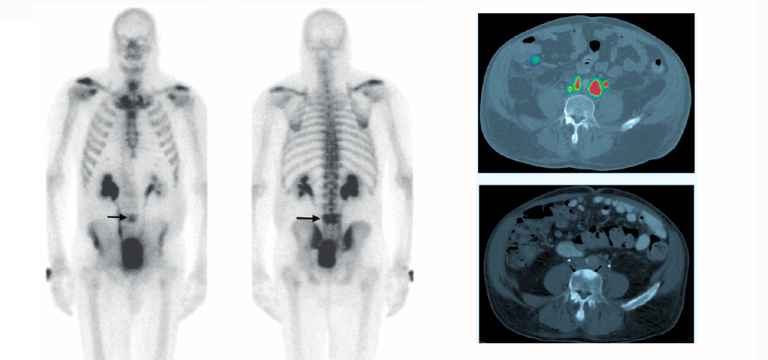

There are two types of pictures a PET/CT camera can take. The PET scan can show the area where the tracer has collected in the body. The CT (computed tomography) scan offers accurate and detailed pictures of the tissues and structures of the body.

18F-Sodium Fluoride (NaF) bone PET/CT scans is extremely helpful in assisting doctors to get a whole-body view of the skeleton. These images provide great help for the detection and examination of metastatic bone cancer. Some of the most common cancers are mainly associated with metastatic bone disease, prostate, breast, and lung cancer, so, assessing bone metastases is important.

- Evaluating metastatic bone disease

- A higher accuracy in the detection of both osteolytic and osteoblastic metastases

- Greater level of differentiation between benign versus malignant lesions

There are certain differences between bone scans and PET/CT in the detection of bone metastases, which can be attributed to the different mechanisms. A bone scan depends on the osteoblastic response to tumor-induced bone destruction, whereas FDG-PET/CT identifies the metabolic activity of the tumor cells.